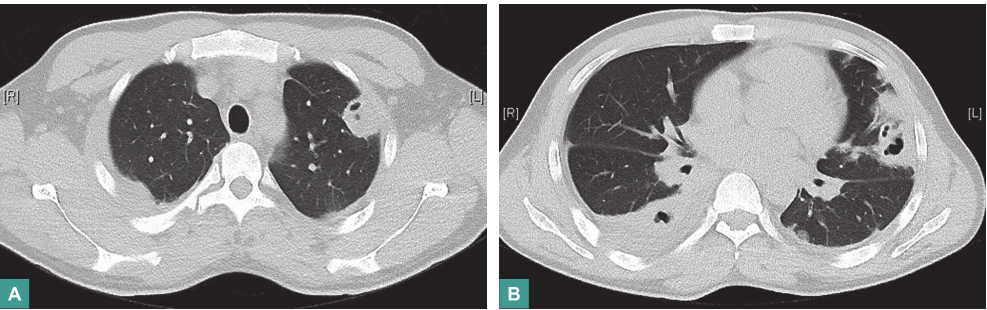

(4)影像学检查

胸部CT平扫和增强扫描示双肺弥漫多发结节及肿块,纵隔内气管前、腔静脉后部分淋巴结轻度增大(图1)。

图1 胸部CT表现

4.影像学检查

胸部CT显示双肺弥漫性多发结节和肿块,上肺部明显,局部病灶有小空洞,纵隔内淋巴结无明显肿大,增强扫描显示肺内病灶无明显强化。